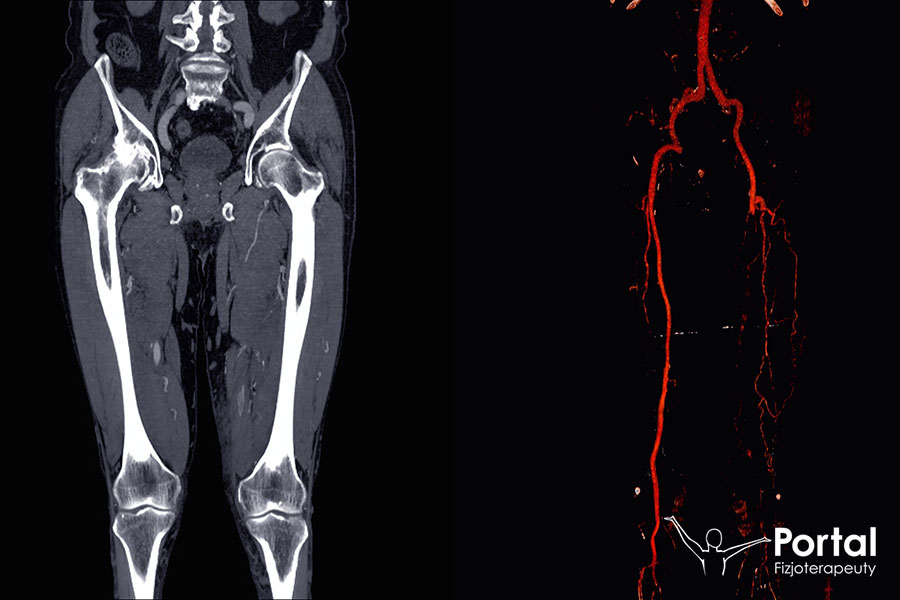

Tętnica biodrowa wspólna

Tętnica biodrowa wspólna (łac. arteria iliaca communis) to bardzo ważna struktura układu naczyniowego w ciele człowieka. Unaczynia narządy miednicy, a […]

Tętnica udowa (łac. arteria femoralis) stanowi przedłużenie tętnicy biodrowej zewnętrznej. Choć patrząc na samą nazwę tej struktury wydawałoby się, że